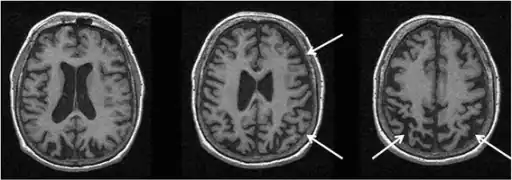

MRI

MRI images are useful in displaying atrophied portions of neuroanatomical positions within the brain. As a result, it is especially effective in identifying regions within different areas of the brain that have been negatively affected due to the complications associated with CBD. To be specific, MRI of CBD typically shows posterior parietal and frontal cortical atrophy with unequal representation in corresponding sides. In addition, atrophy has been noted in the corpus callosum.[19]

Functional MRI (fMRI) has been used to evaluate the activation patterns in various regions of the brain of individuals affected with CBD. Upon the performance of simple finger motor tasks, subjects with CBD experienced lower levels of activity in the parietal cortex, sensorimotor cortex, and supplementary motor cortex than those individuals tested in a control group.[19]